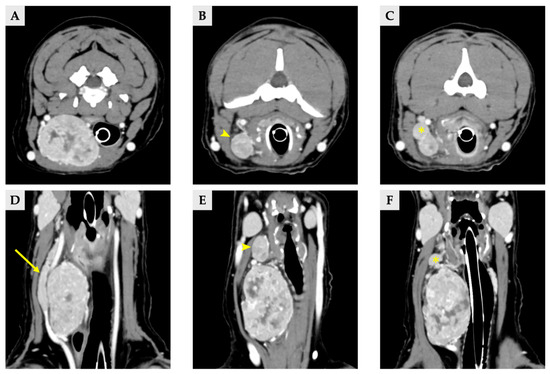

Radiographs demonstrated a soft-tissue opacity over the trachea at the level of C2–C5, causing leftward tracheal deviation (Figure 1). No pulmonary lesions were evident. CT confirmed three well-defined, separate right-sided cervical masses, including the largest palpable cervical mass, extending from the C1 to C5 levels (Figure 2). All three masses were clearly distinct from one another, with no visible continuity on cross-sectional imaging. Mass 1 measured 66.6 mm × 42.0 mm × 37.6 mm (approximately 56 cm3 in volume [14]) and originated from the right thyroid gland. It showed heterogeneous contrast enhancement and produced a filling defect within the adjacent right internal jugular vein, consistent with vascular invasion. Mass 2 measured 25.1 mm × 14.2 mm × 16.5 mm in size, located cranially to mass 1 without any structural connection, and the volume was 3.1 cm3 [14]. Mass 3 measured 11.5 mm × 11.5 mm × 8.6 mm in size, 0.7 cm3 in volume [14] and was positioned between mass 1 and mass2, lying dorsally to mass 2, and was likewise distinctly separated from the other lesions, and the total volume of three masses was approximately 60 cm3 [14]. The left thyroid gland appeared normal, whereas no normal thyroid tissue was identified on the right side at the corresponding anatomical level; instead, only the three masses were present. This finding supports the interpretation that these three lesions originated from the right thyroid gland.

Figure 2.

Delayed phase of CT scan image of three thyroid masses (A–C) transverse view, (D–F) dorsal view. (A,D) Images of right thyroid mass 1, demonstrating a filling effect of right internal jugular vein (arrow). (B,E) Right thyroid mass 2 (arrowhead). (C,F) Right thyroid mass 3, locating between the mass 1 and 2 (asterisk).

No evidence of pulmonary metastasis was identified on CT, and the regional lymph nodes showed normal size and homogeneous contrast enhancement. However, both adrenal glands were enlarged (left: 14.1 mm cranial pole, 9.5 mm caudal pole; right: 9.3 mm cranial pole, 5.7 mm caudal pole) while retaining a normal adrenal waist configuration in ultrasonography and CT scan.